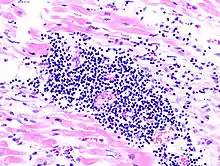

Virale Myokarditis

Ät.: Coxsackie-, ECHO-, Adenoviren, Influenzaviren

Pathogenese: Herzmuskelnekrose durch Virus und T-Zell-vermittelte Immunreaktion.

Mikro: Interstitielles lymphozytäres Infiltrat (kleine blaue Zellen), kaum Nekrosen.

![]() Virale Myokarditis bei Patient mit plötzlichem kongestiven Herzversagen, Autopsiepräparat, H&E. |

![]() idem. |